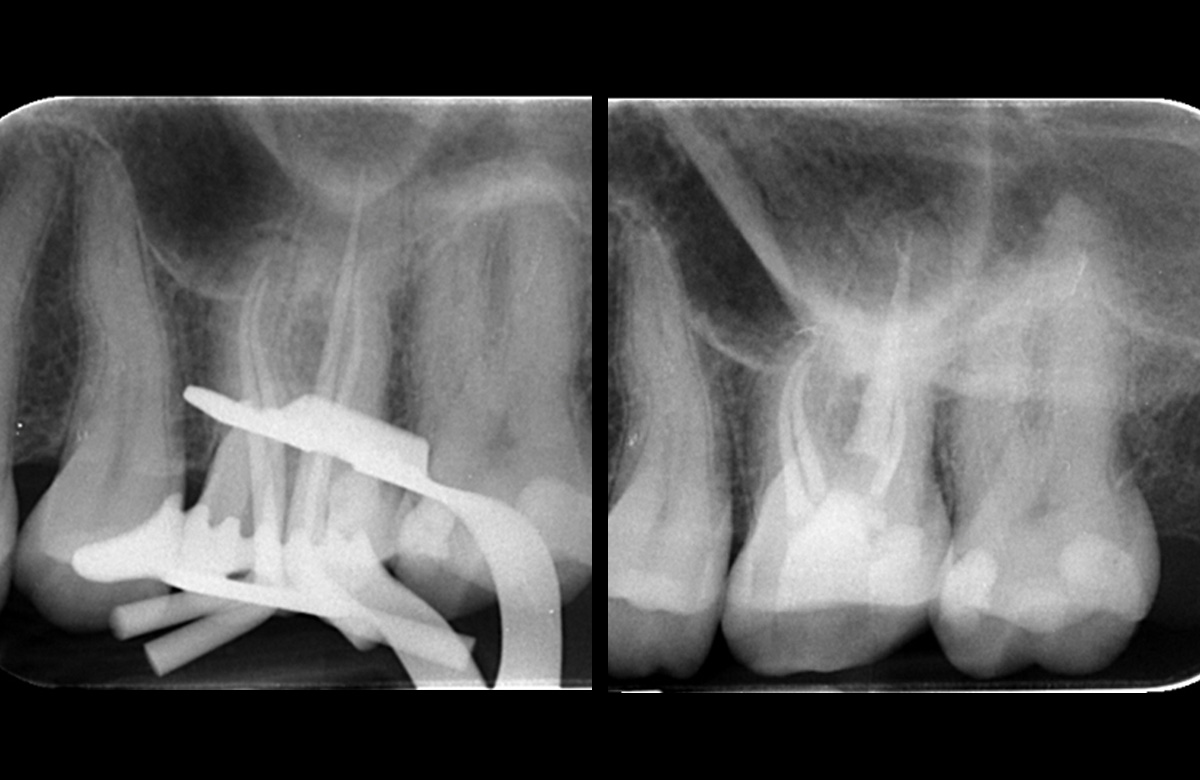

Pre operative periapical radiograph of the tooth 16

Pre obturation periapical radiograph of the tooth 16, checking cone length